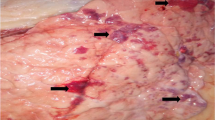

Postmortem findings on 8 out of 30 infected animals showed different PM lesions (Table 1). C. perfringens was recovered from lung samples of only six cases. Briefly, on blood base agar with 7% sterile blood, C. perfringens colonies were 2–3 mm in diameter, rounded, raised, glistened, and showed double zone of hemolysis. On TSC agar, C. perfringens colonies were black in color. Microscopically, C. perfringens isolates appeared to be Gram-positive short plumb bacilli rarely having central oval non-bulging endospores. Biochemical tests were confirmative to C. perfringens, while multiplex PCR revealed presence of C. perfringens alpha toxin gene (Fig. 1).

To the best of the author’s knowledge, this is the first study that reports Clostridium infection as a complication of FMD in buffalo and cattle worldwide. Although pneumonia related to C. perfringens has rarely been described (Chen et al. 2011), the respiratory distress by clinical examination and pneumonia by postmortem examination in FMD-infected cattle and buffalo complicated with C. perfringens infection observed in this study is coincided with previous report that documented C. perfringens to affect the respiratory system as it causes severe acute pulmonary edema, which was particularly marked in the interlobular septa in calves (Constable et al. 2016), lung edema in mouse (Fernandez-Miyakawa et al. 2007), interstitial pneumonia, purulent fibrinous bronchopneumonia, abscess, and interlobular fibrosis sick calves and cow cattle (Sasani et al. 2013). Moreover, the presence of necrotizing pneumonia in a woman due to C. perfringens was previously recorded (Palmacci et al. 2009). The complications with bacterial infections in such cases might be attributed to the suppression in the body immunity that is associated with viral infection as previously proposed (Francoz et al. 2015; Grubman and Baxt 2004; Howard 2007). Moreover, outbreaks of respiratory form of hemorrhagic septicemia (HS) followed FMD in the same animals have been reported (Verma et al. 2004). Preceding FMD infection probably lowers the resistance to diseases or causes stress on the animals, leading to precipitation of HS. Several predisposing factors for systemic clostridial dissemination include intraoral pathology (carious teeth or gingival disease) and intrabdominal pathology such as malignancy and enteric vascular malformation (Craven 1989; Tanabe et al. 1989).